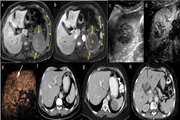

Liver hydatidosis disease with portal vein invasion: Report of a rare case and review of literature 1403/12/26 - 08:40